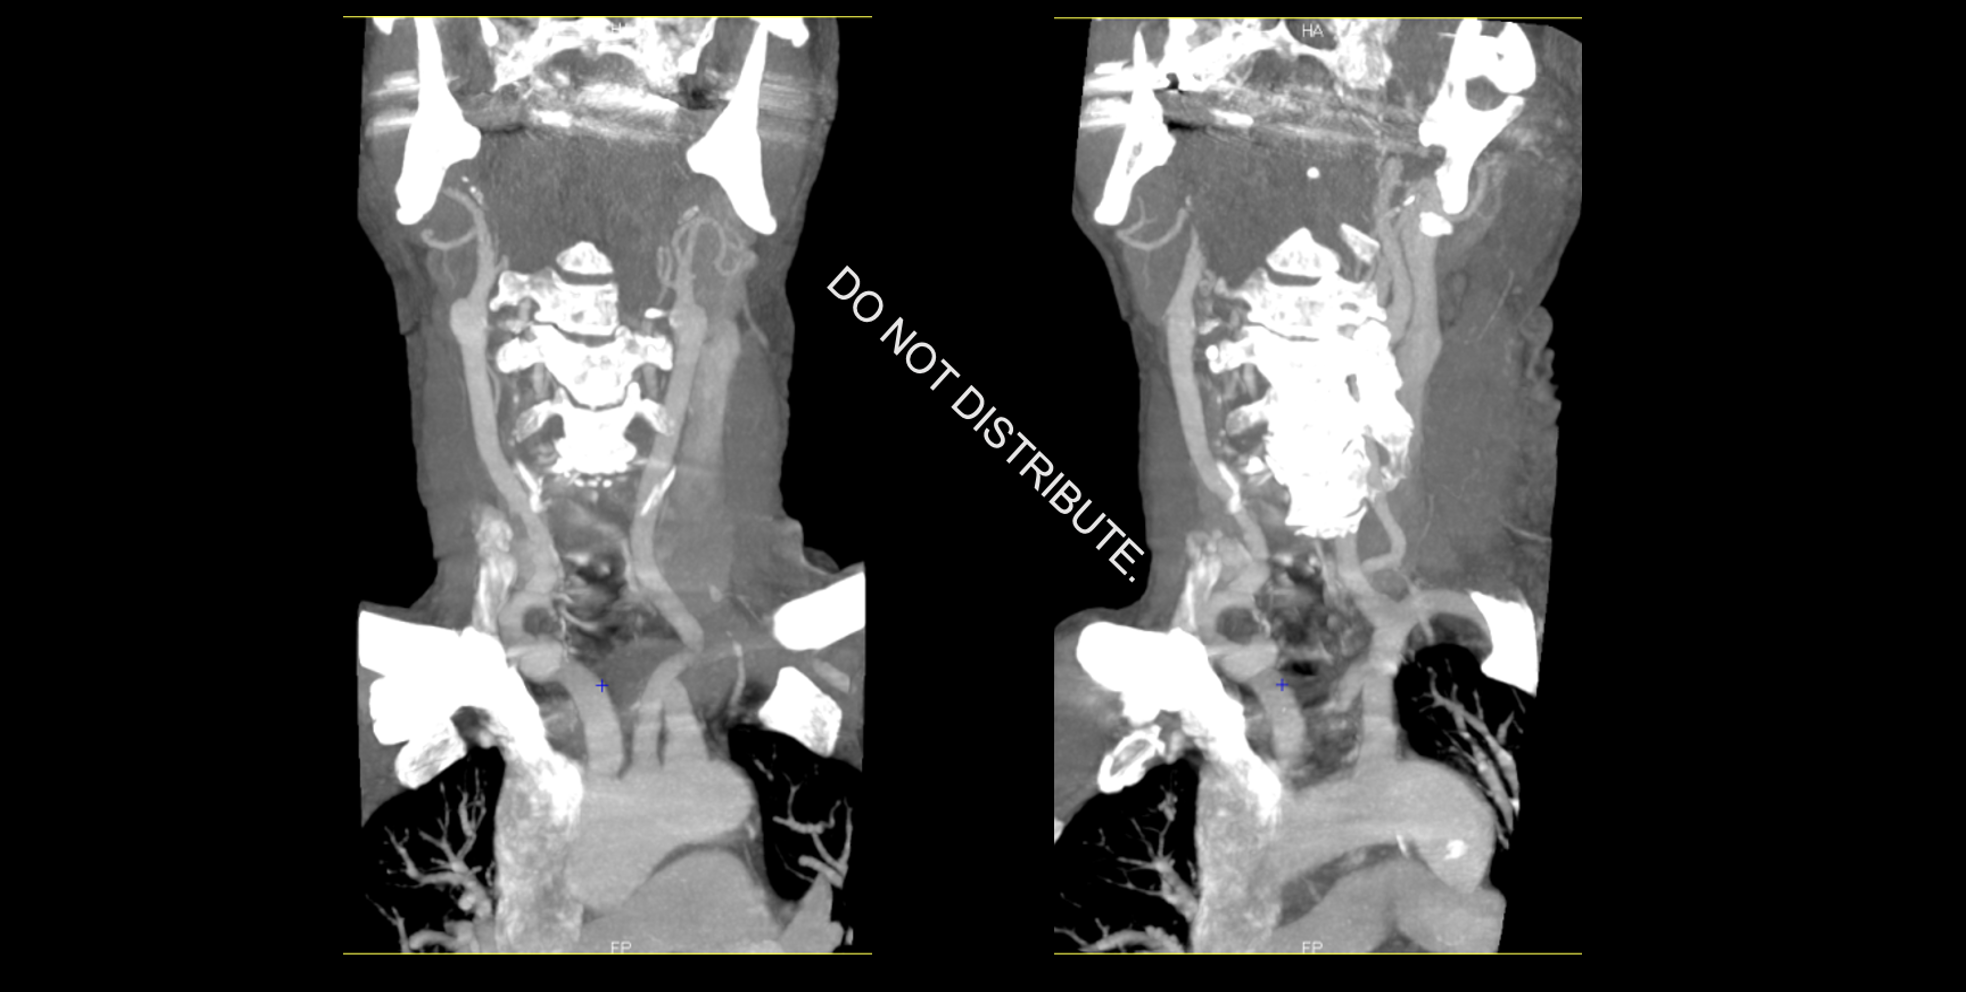

Methods

• OPTIMISE is a pan-Canadian prospective registry of patients treated with EVT across 20 sites and 7 provinces between 2018-01 and 2022-12.

• Using OPTIMISE data, we compared men and women with regards to baseline characteristics, functional outcomes and, as our primary outcomes, procedural complications and sICH

• sICH was defined  as a ≥4-point increase in the NIHSS score associated with the presence of parenchymal hematoma type 1 or 2 on follow-up CT, as determined by the treating physician

Results

3631 patients were included for analysis:

• Women were older (71.8±14.6 vs 68.0±13.1 years, p<0.001).

• There were no differences in median time from onset to puncture {232 (155-365) men vs. 235 (163-377) women, p=0.159}, and from puncture to reperfusion between sexes {(25 (17-37) vs. 24 (17-37), p=0.984}.

•  There were no differences in sICH rates {44 (2.5%) vs. 37 (2%), p=0.388}.

• Procedural complication rates were not different between men and women (5.8 vs 5.6% p=0.76)

Men

(N=1778)

Women

(N=1853)

p-value

Age (mean±SD)

68.0±13.1

71.8±14.6

0.001

Median (IQR) onset to puncture - min

232 (155-365)

235 (163-377)

0.159

Median (IQR) puncture to reperfusion - min

25 (17-37)

24 (17-37)

0.984

Tici 2b3

1446 (81.3%)

1554 (83.9%)

0.319

Tici 3

898 (50.5%)

1021 (55.1%)

0.264

sICH

44 (2.5%)

37 (2%)

0.388

Complications

• Dissection

• Perforation

• Embolization

• Arterial access

26 (1.5%)

11 (0.6%)

25 (1.4%)

45 (2.5%)

30 (1.6%)

7 (0.4%)

25 (1.3%)

43 (2.3%)

0.804

0.426

0.996

0.761

Table: Baseline characteristics in male and female

Bleeding complications in ischemic stroke3 e1619443612145